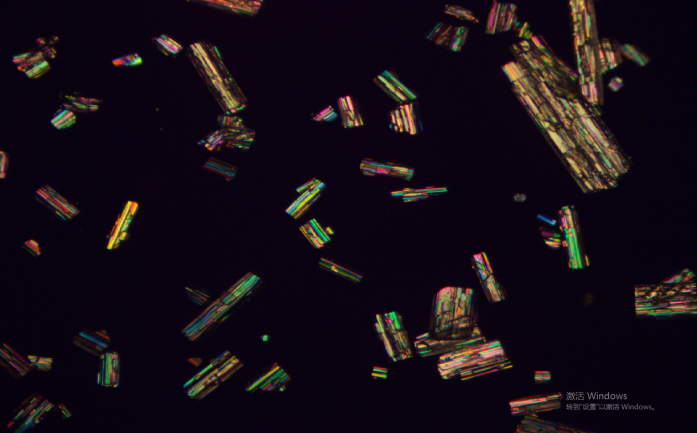

5.可以分析偏光下,偏光顆粒的粒度,粒形分析;